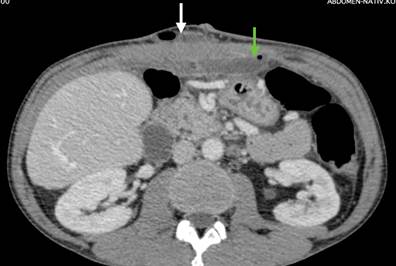

Выполнена операция TAR с имплантацией стандартной полипропиленовой сетки 30х30 см. Этапы вмешательства соответствовали общепринятым для задней сепарации [5]. Осуществлена профилактика инфекций области хирургического вмешательства (ципрофлоксацин 400 мг внутривенно перед вмешательством и далее 2 раза в сутки) и венозных тромбоэмболических осложнений (эноксапарин 0,4 мл подкожно 1 раз в сутки). Активизирован в 1-е сутки после операции. На 5-й день отмечена лихорадка до 39 ºC. Уровень C-реактивного белка 347 мг/л. Тест на COVID-19 отрицательный, на фронтальной рентгенограмме легких инфильтративных изменений нет. Терапия препаратом имипенем/циластатин оказалась совершенно неэффективной. На КТ обнаружены большие жидкостные скопления с пузырьками газа, расположенные ретромускулярно и в ране (рис. 9).

Рис. 9. КТ второго пациента после операции. Белой стрелкой показано жидкостное скопление с пузырьками газа в ране, зеленой стрелкой показано жидкостное скопление с пузырьками газа в ретромускулярном пространстве

Во втором клиническом случае для оценки ситуации была применена КТ, которую следует расценивать как наиболее эффективный метод диагностики [6, 20, 21]. Однако трактовка результатов вполне могла быть иной. Жидкостные скопления в послеоперационном периоде обычно рассматриваются как абсцессы (если есть системная воспалительная реакция), гематомы или серомы (если признаков воспаления нет) [6, 20]. В большинстве случаев наличие обширных жидкостных скоплений с пузырьками газа с признаками системной воспалительной реакции является аргументом к немедленной ревизии раны. В данной ситуации включения газа расценены как остатки воздуха в ране после операции. Клинически заподозрена MRSA-инфекция, далее с помощью целевой антибиотикотерапии все имеющиеся проблемы были решены без пункций и вмешательств. Данный пример демонстрирует возможность и эффективность консервативного подхода к лечению воспалительного осложнения.